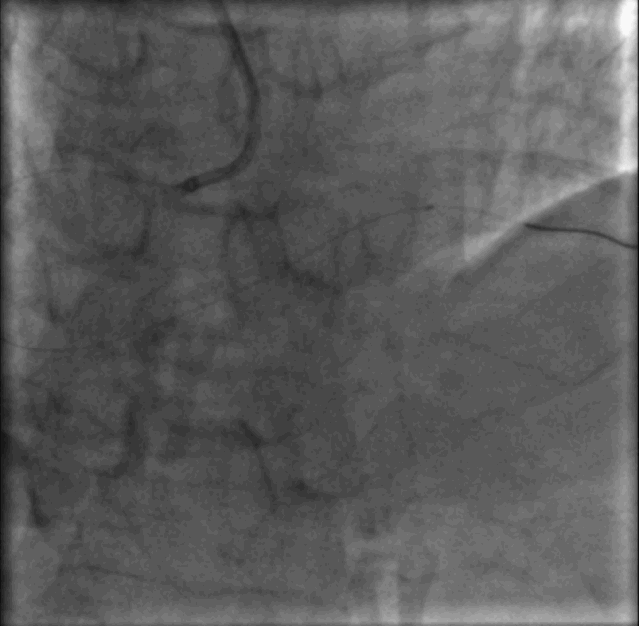

介入治疗术前、术后对比

术后用药

术后症状消失

术后2天出院

常规药物治疗

DAPT1个月

随访持续中